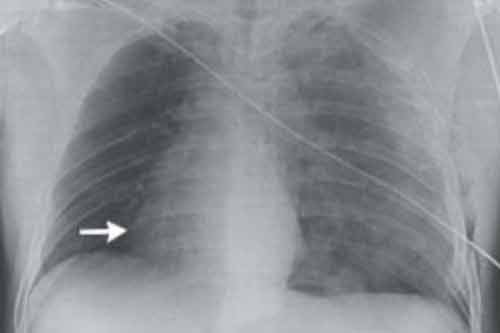

Khi nạn nhân được đưa đến bệnh viện, các bác sĩ cấp cứu phát hiện rằng trái tim của người đàn ông này đã dịch chuyển khi họ tìm cách nghe nhịp tim. Hình ảnh chụp X-quang cho thấy tim nạn nhân đã xoay chuyển 90 độ về bên phải. Ngoài ra, động mạch chủ và động mạch phổi của nạn nhân đã quay về bên phải.

| Tim bệnh nhân xoay 90 độ sau tai nạn. |

| Hình ảnh (trái) cho thấy trái tim xoay lệch 90 độ về bên phải và trở lại bình thường (phải). |